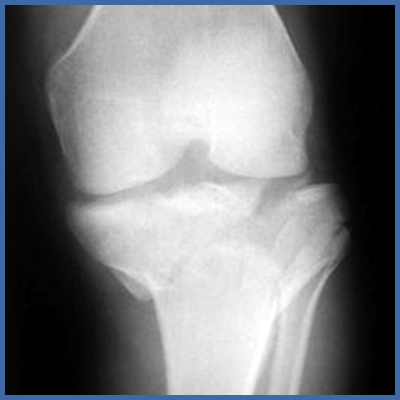

Verletzung des Unterschenkels mit Beteiligung des Kniegelenkes; genauer eine Tibiaplateau-Fraktur. Zusätzliche Strukturen wie Kreuz-, Seitenbänder oder Mensikus können verletzt sein. Die Harmonie der Gelenksfläche ist ebenfalls zerstört.